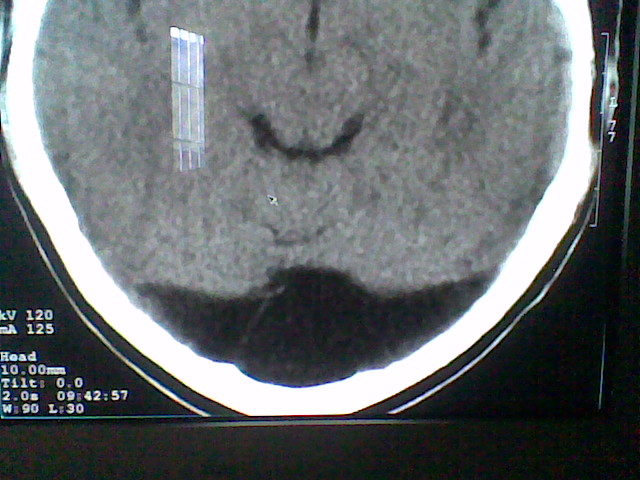

患者,男,头晕4天来诊,要求ct。

大枕大池合并蛛网膜囊肿。

支持 大枕大池合并蛛网膜囊肿。

考虑大枕大池合并蛛网膜囊肿。

有没有dandy-walker综合征的可能?